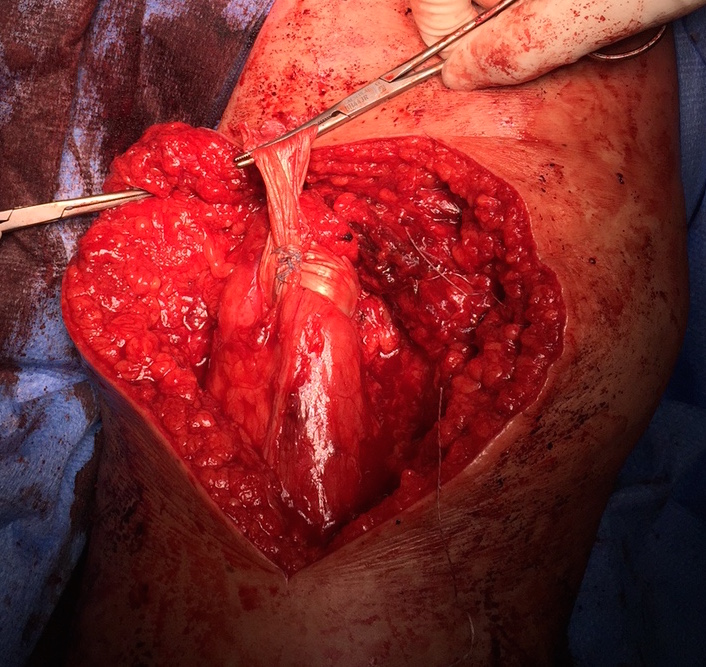

Hamstring (*) with sciatic nerve lateral to hamstring (blue vessiloop)

Identify and release proximal hamstring tendon

Stump of the conjoint tendon (*)

Sciatic nerve with blue vessiloops

Pulvetaft weave tendon through the strongest, thickest part of the stump